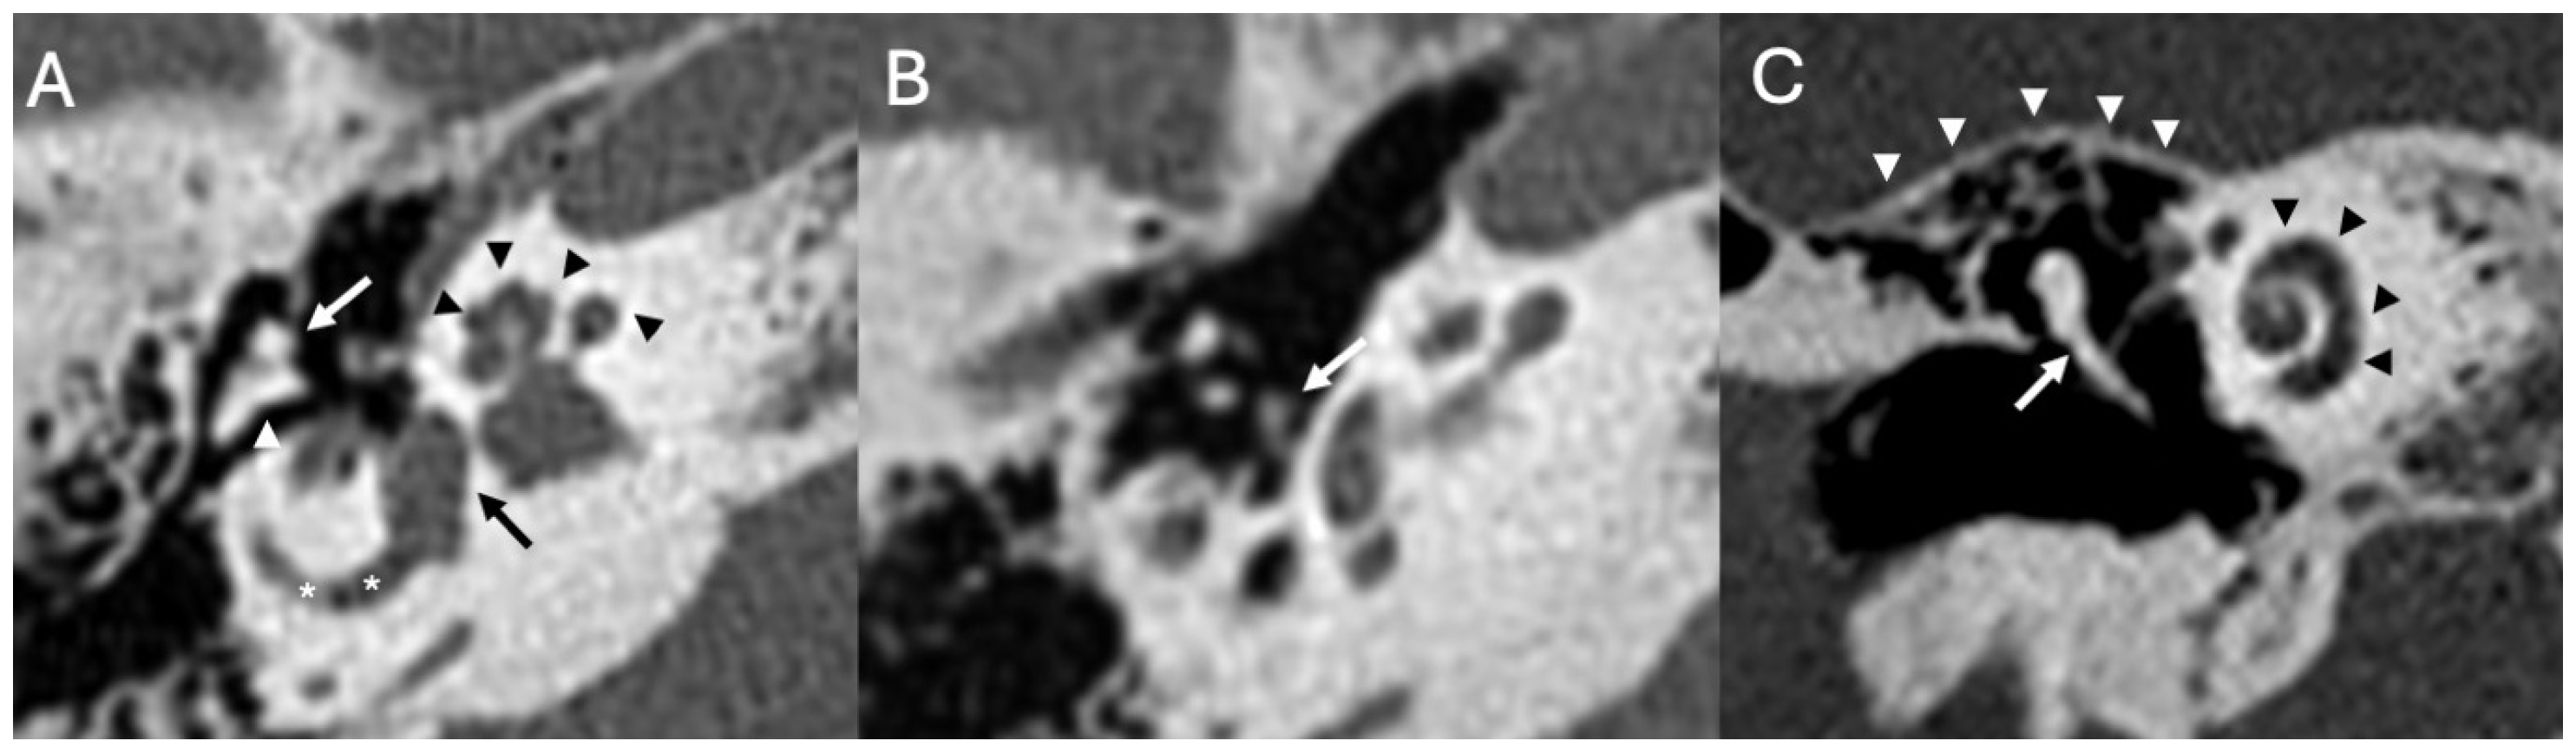

3.3. Cholesteatoma

3.3.1. Imaging

3.3.2. Complications

| Cholesteatoma and Otogenic Complications | Kuo et al., 2015 [26]; Baráth et al., 2011 [27]; Mustafa et al., 2014 [28]; Dubey et al., 2010 [29]; Sun et al., 2014 [30]; Lee et al., 2020 [31] | Reviews and retrospective studies | Cholesteatoma causes erosion and CSF leak, leading to meningitis (12–30% incidence); MRI improves detection; pediatric risk emphasized. |